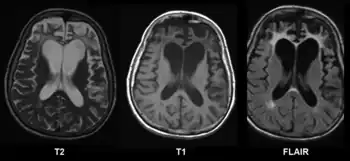

Brain MRI of a 65-year-old female person with frontotemporal dementia. Cortical and white matter atrophy of the frontal lobes is clear in all images. | |